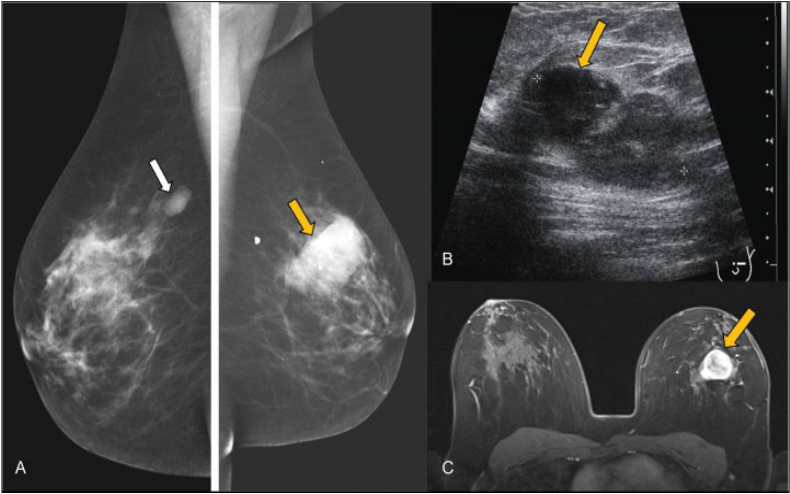

Tumor Phyllodes. Mujer de 45 años con antecedente de fibroadenoma en mama derecha que acudió por nódulo palpable de nueva aparición en mama izquierda. (A) Mamografía digital. Nódulos bilaterales, el de mayor tamaño en cuadrante superior externo (CSE) de mama izquierda (flecha amarilla). (B) Ecográficamente es un nódulo sólido, de bordes lobulados y ecogenicidad heterogénea (flecha), con zonas de buena transmisión del sonido. (c) RM con contraste iv. Nódulo hipervascular de bordes bien definidos (flecha). Tanto en la BAG como en la extirpación completa, el resultado histológico es de Tumor Phyllodes.